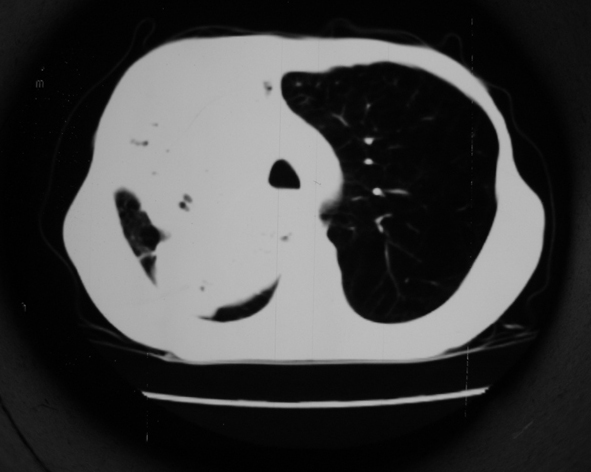

男53岁,咳嗽气短,以往身体健康.

右肺上叶多发多形态空洞及增殖灶,可见团块钙化,胸膜肥厚、粘连,考虑继发型肺结核可能性大

1.右肺上叶干酪性肺炎,2。肺气肿,肺大泡

1.右肺上叶干酪性肺炎,2。肺气肿,肺大泡。支持!

支持右上肺继发性肺结核并干酪性肺炎,右肺大泡,左肺代偿性气肿。